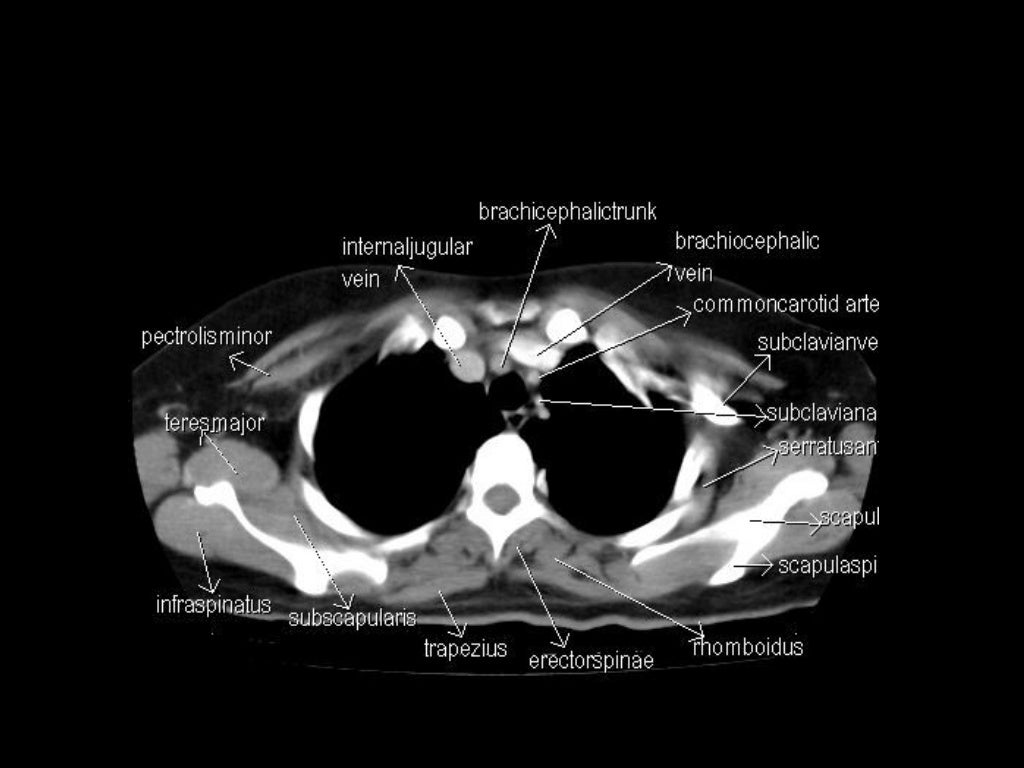

Computed tomography (CT) scanning is an extremely common imaging modality in modern medicine.With advancements in technology, it is rapidly replacing many diagnostic radiographic procedures. In this article, we will outline the basic science behind CT scans, describe the principles of interpretation, and highlight their advantages and drawbacks compared to other imaging techniques. e-Anatomy is a high-quality anatomy and imaging content atlas.It is the most complete reference of human anatomy available on the Web, iPad, iPhone and Android devices. Explore detailed anatomical views and multiple modalities (over 8,900 anatomic structures and more than 870,000 translated medical labels) with images in CT, MRI, radiographs, anatomical diagrams and nuclear images. This article lists a series of labeled imaging anatomy cases by body region and modality. Brain CT head: non-contrast axial CT head: non-contrast coronal CT head: non-contrast sagittal CT head: non-contrast axial with clinical questions CT

Normal chest x ray. Radiological anatomy is where your human anatomy knowledge meets clinical practice. It gathers several non-invasive methods for visualizing the inner body structures. The most frequently used imaging modalities are radiography (X-ray), computed tomography (CT) and magnetic resonance imaging (MRI).X-ray and CT require the use of ionizing radiation while MRI uses a magnetic CT Scan Anatomy Overview. CT scans, or Computed Tomography scans, are essential tools in modern medicine. They provide detailed images of the inside of your body and are particularly useful for diagnosing conditions that affect the bone and soft tissues. Understanding CT scan anatomy is crucial for interpreting these images accurately.